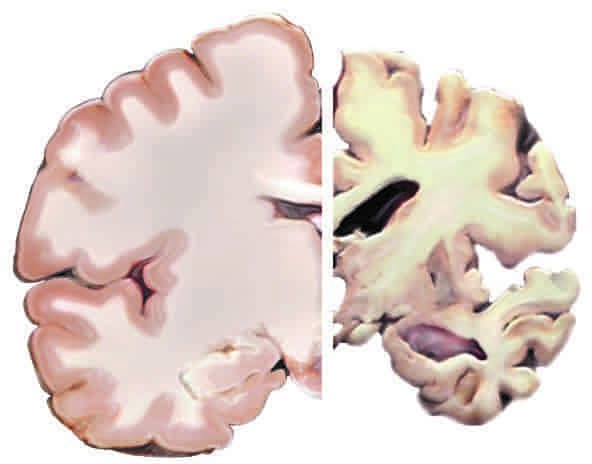

Se trata de un deterioro que se da de forma progresiva por el que, poco a poco, las células cerebrales van degenerándose hasta que terminan muriendo. A pesar de que no existe cura, sí se puede ayudar a los pacientes a través de diversos métodos.